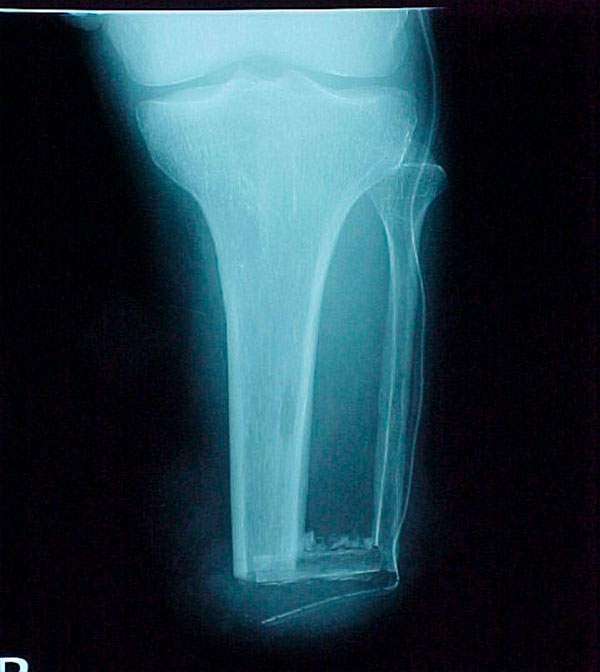

- Focus Area Reconstructive Surgery & Non-Surgical Management to Improve Bone Healing

- Sponsor DoD PRORP

- Primary Objective Observational study comparing outcomes following limb salvage versus amputation of a severe distal tibia, ankle, and/or foot trauma